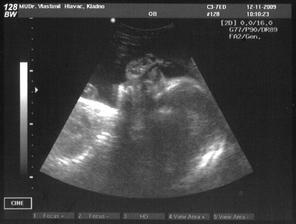

*12.11.2009: Na ultrazvuku všechno v pořádku. Synáček už je hlavou dolů, tak doufejme, že tak vydrží. Pokud jde o moji už téměř invalidní chůzi, jak jsem předpokládala, prý mi nikdo nepomůže...leda nahřívat.